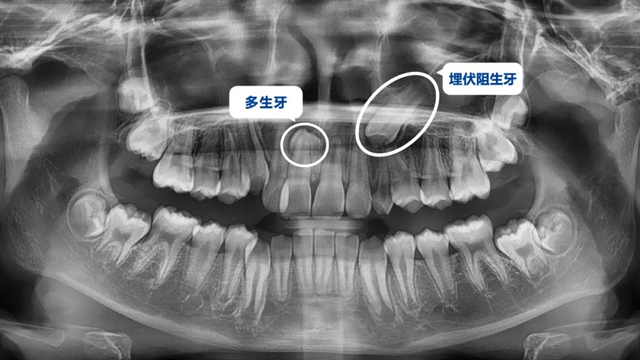

这位小患者的口腔问题包括:牙列不齐,个别门牙反颌,左上尖牙完全埋伏阻生,另外,CBCT显示右上门牙牙根腭侧内还有一颗多生牙。

简单地说,牙齿不整齐只是小问题,他更大的问题是:在不该长牙的地方多长了一颗牙,而乳尖牙滞留,早该替换出来的尖牙长不出来,这两颗牙的问题如果不及时干预治疗,会带来很多长期的口腔问题。

据了解,位于腭侧的多生牙紧挨着已经替换完的1号恒牙(门牙),如不拔除会影响整个牙列的整齐度,后期也可能损伤1号牙的牙根,导致这颗牙齿松动甚至脱落。